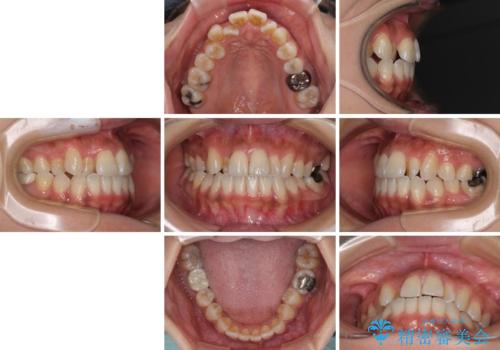

- 上の歯の歯並びを気にして来院された患者様です。

上顎骨の横幅が狭く、歯列が混み合っていたため、急速拡大装置により側方拡大し、咬み合わせと歯列を改善することとしました。

下顎は部分的に咬み合わせに問題があったため、部分的な装置を付けることとしました。